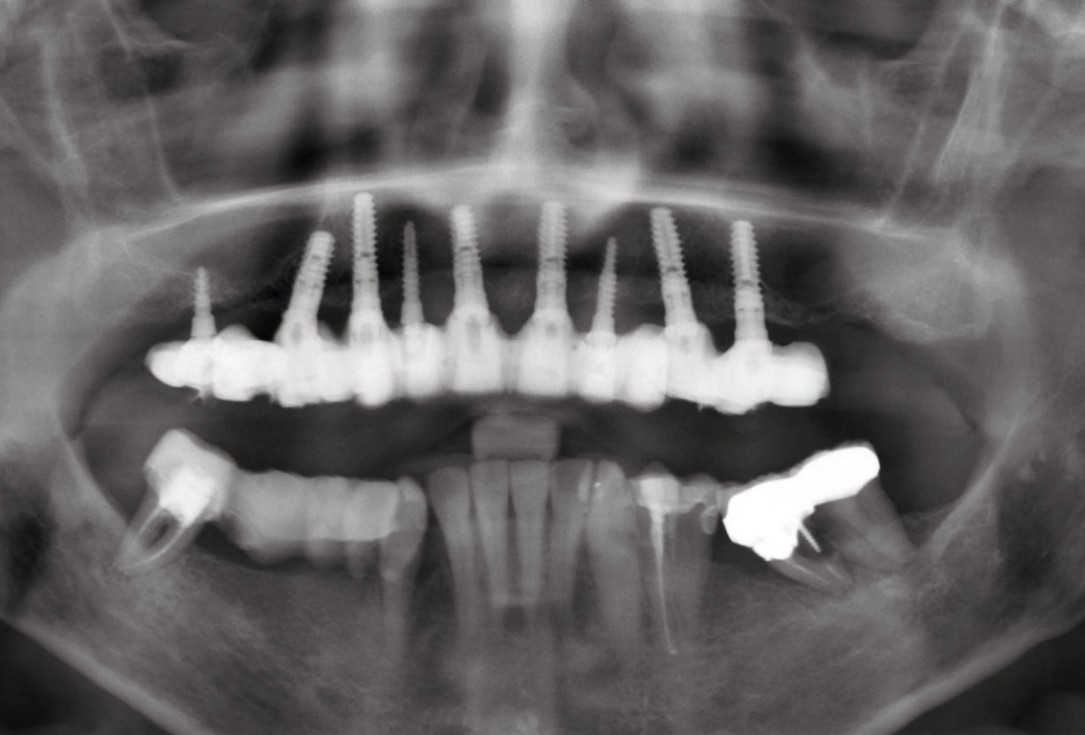

01 / 20 - OPG of the initial situation – provision of missing denture in regio 44 to 47 by a resin-retained bridgeHorizontal ridge augmentation with maxgraft® cortico - M.Sc. E. Kapogianni

OPG of the initial situation – provision of missing denture in regio 44 to 47 by a resin-retained bridge